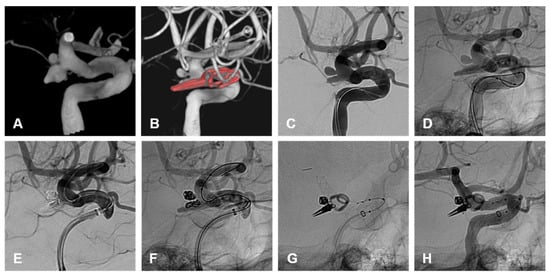

Figure 3. (AC) demonstrate lateral angiographic images from the initial treatment of an unruptured AChoA aneurysm with primary coiling. (A) demonstrates a 4 mm smooth and saccular AChoA aneurysm that incorporates the origin of the AChoA at its neck. (B,C) are the unsubtracted and subtracted images of the final coil mass demonstrating a mRRC II and patency of the AChoA. (DF) demonstrate the lateral angiographic images of the second treatment with coiling and flow diversion following recurrence. (D) is the unsubtracted image demonstrating coil compaction with an enlarged neck residuum prior to retreatment. (E) demonstrates the unsubtracted image of the final coil mass and flow diverter. (F) demonstrates the final subtracted angiographic run post re-treatment with coiling and flow diversion with preserved patency of the AChoA and some filling of the coil interstices. Follow up MRA at 3 months demonstrated complete occlusion of the aneurysm.

A total of 6/31 patients (19%) were retreated while 25/31 (81%) did not have a recurrence or need retreatment. Within the endovascular cohort, 3/24 (12.5%) patients required retreatment and 21/24 (87.5%) did not require any further treatment on follow-up (Table 3). Of those requiring retreatment, 2/3 (66%) were ruptured on initial treatment (Figure 1). One patient was initially treated with primary coiling and retreated by flow diverter stent, following recurrence after 5 months. The second patient was initially treated with primary coiling and was retreated with clipping due to recurrence after 3 months. Of these, 1/3 (33%) were unruptured on initial treatment with primary coiling and were retreated with a flow diverting stent (Figure 3).

One unruptured aneurysm, with a size of 11 mm and neck size of 3.2 mm, underwent primary coiling with mRCC of II. This residuum enlarged after 4 years and was retreated electively with FDS. In medium to large size unruptured AChoA aneurysms, FDS may be considered initially [15,16,17].